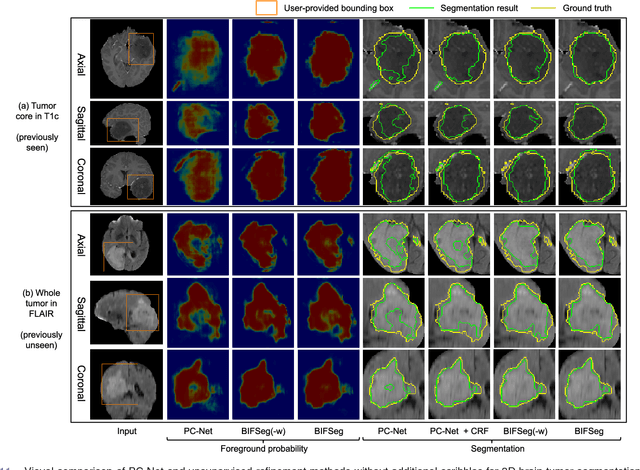

Abstract:Convolutional neural networks (CNNs) have achieved state-of-the-art performance for automatic medical image segmentation. However, they have not demonstrated sufficiently accurate and robust results for clinical use. In addition, they are limited by the lack of image-specific adaptation and the lack of generalizability to previously unseen object classes. To address these problems, we propose a novel deep learning-based framework for interactive segmentation by incorporating CNNs into a bounding box and scribble-based segmentation pipeline. We propose image-specific fine-tuning to make a CNN model adaptive to a specific test image, which can be either unsupervised (without additional user interactions) or supervised (with additional scribbles). We also propose a weighted loss function considering network and interaction-based uncertainty for the fine-tuning. We applied this framework to two applications: 2D segmentation of multiple organs from fetal MR slices, where only two types of these organs were annotated for training; and 3D segmentation of brain tumor core (excluding edema) and whole brain tumor (including edema) from different MR sequences, where only tumor cores in one MR sequence were annotated for training. Experimental results show that 1) our model is more robust to segment previously unseen objects than state-of-the-art CNNs; 2) image-specific fine-tuning with the proposed weighted loss function significantly improves segmentation accuracy; and 3) our method leads to accurate results with fewer user interactions and less user time than traditional interactive segmentation methods.